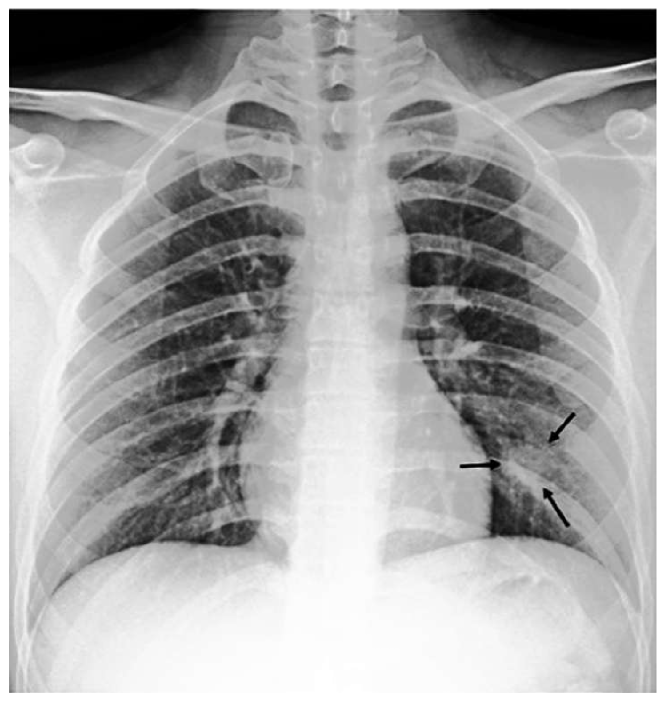

While text removal methods can prevent overfitting, we can simply force the model to look into the lungs in order to address both problems in one effort. To accomplish this task, a U-Net based segmentation illustrated in Fig. 4 is applied to the input images before enhancements. Visualization results for COVID-CXNet with the ROI-segmentation block are shown in Fig. 18.

Refer to caption

Figure 18: Grad-CAM visualization of the proposed model, trained with lung-segmented CXRs, over sample cases.

A figure with more Grad-CAMs is attached in Appendix B. From Fig. 18, it can be observed that COVID-CXNet with ROI-segmentation has delivered superior performance regarding the localization of pneumonia features. Worthwhile to mention that image augmentation is expanded by adding zoom-in, zoom-out, and brightness adjustment. Label smoothing is also applied to the loss function.

The proposed method has shown a negligible drop in metric scores; accuracy is decreased by 0.42%, and f-score is declined by 0.02. This decrease is a result of training with a larger dataset and accurately segmented ROIs, which means it has become more robust against unseen samples. There is a trade-off between catching good features and higher metric scores; while better features result in a more generalized model, high metric scores may indicate overfitting.